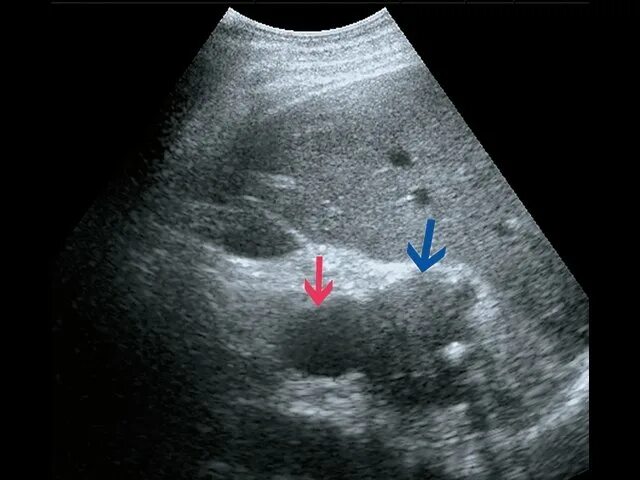

Кальцинат узи